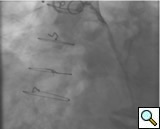

PCI of the vein and arterial grafts have unique challenges. For any PCI, guide support is very important for successful balloon and stent delivery. In a tortuous vein graft with a steep angle, advancement of a stent can be very difficult and challenging. Therefore, it is important to choose the best available catheter before starting PCI. Similar to the right coronary angiography, a JR4 guide catheter is most commonly used in this setting. However, Amplatz guide catheters for left vein grafts and multipurpose catheters for right vein grafts are better choices in certain anatomy. In Figure 8 and Figure 10 two examples of poor guide support in two vein graft interventions can be seen. Initially, a JR4 guide was used for PCI of the vein graft supplying the left anterior descending artery (LAD) without any success. However, after changing the guide to an Amplatz left 2 guide catheter, we achieved excellent support without any difficulty in advancing two stents (Figure 9). In Figure 10, difficulty is illustrated in engaging the vein graft ostium supplying the right coronary artery with a JR4 catheter. This vein graft has a very steep inferior take off from the aorta. After changing the guide to a multipurpose catheter, we were able to deliver three stents successfully without any difficulties (Figure 11). Similar challenges exist in the treatment of the left IMA or right IMA. These arterial grafts can be extremely tortuous making stent delivery very difficult. It may be necessary to use short length stents for a better deliverability or stents with lowest profile. Usually, similar to the native coronary intervention, a 6 French guide is appropriate for the routine use.

In order to minimize distal embolization, primary stenting without previous angioplasty is recommended in vein graft interventions. However, in angulated and very high grade lesions, stent without balloon angioplasty may not be able to cross a lesion requiring balloon angioplasty before stenting. Balloons should be sized smaller in order to prevent rupture or dissection. Once an angioplasty balloon is advanced across the lesion, usually it is inflated to 6 or 8 atmospheres for few seconds. Stenting is similar to the balloon. Once a stent is placed across the lesion, it is inflated to higher pressures such as 12-14 atmospheres. The use of a bare metal or drug eluting stents in vein grafts is controversy. This topic is discussed in detail in the restenosis chapter. Angioplasty and stenting of bifurcation sequential vein grafts at the site of the bifurcation or distal to the graft is challenging and usually requires more complex interventions including double wiring and utilization of two stents. A comprehensive classification with guide to interventional techniques for bifurcation lesions is published recently that can be used as a guide for bifurcation lesions interventions involving vein grafts [1].